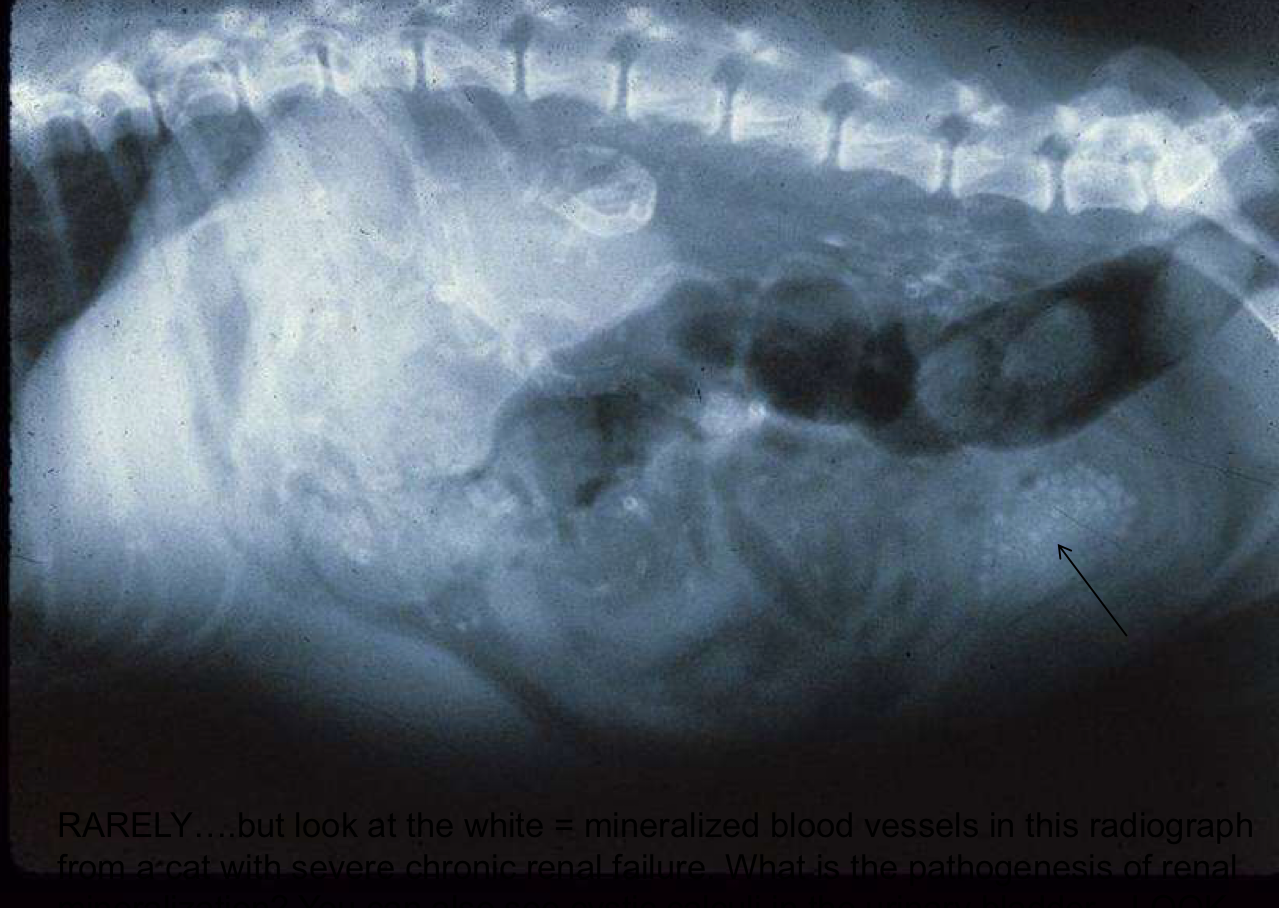

How is this lesion formed in renal failure patients?

Hyperphosphatemia due to decreased renal excretion leads to mineralization of soft tissues.

Mineralization of the vessels in a patient with renal failure. How can this be predicted and prevented?

Predict with labs: Ca x P level = .70 (risk for mineralization)

Prevent by lowering serum phosphorus levels (Phos-bind)